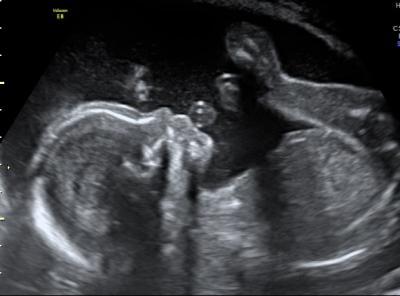

Hallo ihr! Ich bin zurück vom zweiten großen Ultraschall. Es ist alles gut :-) Es wird ein Mädchen werden, was ja aber schon zwei andere Ärzte bestätigt haben. In zwei Wochen geht es noch zum Fein-Ultraschall. Mein Arzt meint, er ist dann beruhigter, weil ich ja gern daheim entbinden möchte. Hat das jemand machen lassen von euch und weiß wie viel das kosten wird, oder ob das die private Krankenversicherung zahlt? Ich häng euch mal noch zwei Bildchen an :-) Auf dem einen macht sie grad ne Spucke-Blase und auf dem anderen, sieht man mal wieder überdeutlich, dass es ein Mädchen wird (ich hoffe ihr erkennt das auch :-) ) Bin echt froh, dass alles gut ist. Nächste Woche geht es wieder in die Schule, dann schauen wir mal, wie es mir da geht.

Hier noch das zweite Bild :-)